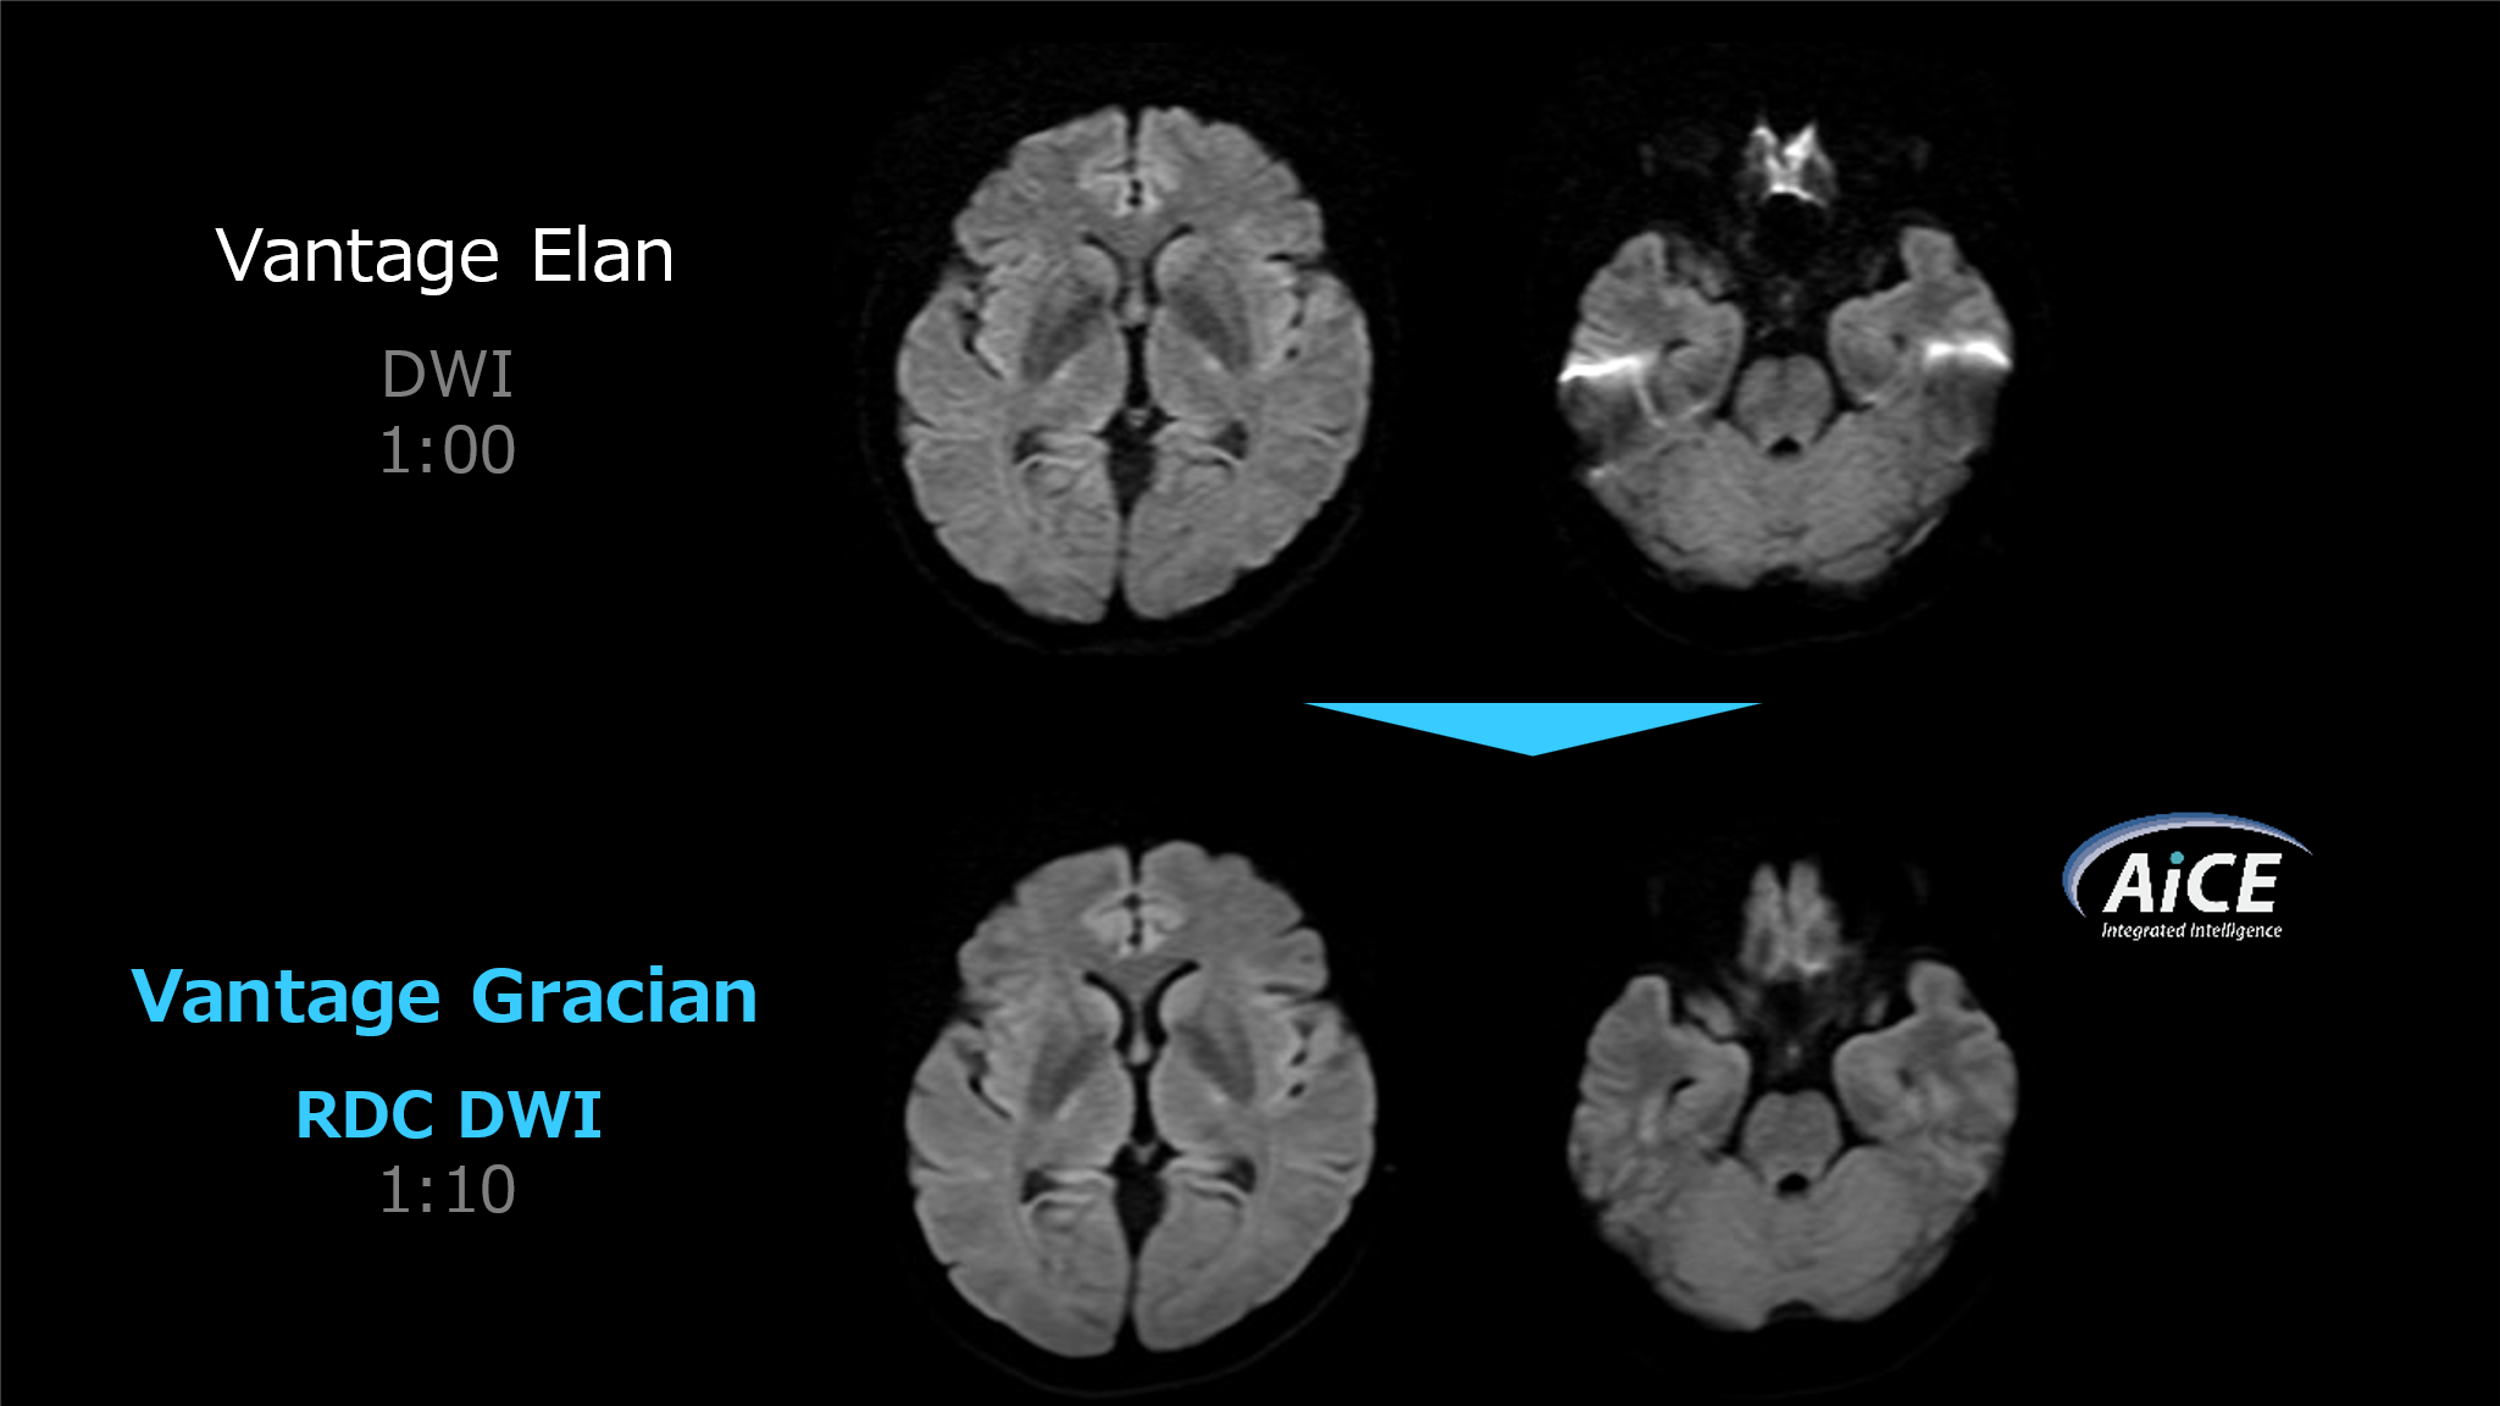

高画質化の面では、新たに搭載されたDWIの歪み改善技術である「RDC DWI」による改善効果が顕著であり、ルーチン検査において全例で使用しています。類似機能に「FASE DWI」もありましたが、コントラスト変化や撮像時間延長が伴うため、ルーチンでの使用が困難でした。一方、「RDC DWI」は、コントラストに影響を与えることなく、撮像時間の延長も約10秒にとどまり、実用性が非常に高いと感じています。DWIは非常に重要なシーケンスであり、わずかな時間延長で画質を大きく改善できる点は、臨床上、大きなインパクトになりました。(Fig.5)